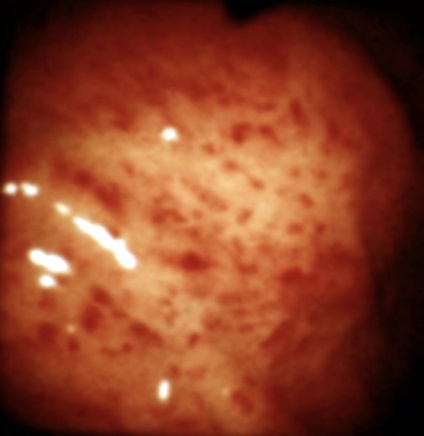

Diffúz krónikus gyomorhurut - tünetei, gyógyszeres kezelés és diéta

Krónikus diffúz gyomorhurut, bár úgy vélik, gyakorlatilag ártalmatlan betegség, de van osztva több szakaszból áll, ami azt jelenti, hogy a betegség nem megfelelően kezelt fog át az egyik szakaszban, hogy egy másik, súlyosabb, ami irreverzibilis pusztulását a nyálkahártya a gyomor. A betegség összesen három szakaszból áll:

- Az első szakaszban. A betegségre jellemző a felületes gyulladás a gyomor nyálkahártyáját. Bevétel kevés vagy semmilyen tünettel, így nagyon nehéz megfigyelni egy időben.

- A második szakaszban. Kísért a lassulás a helyreállítási sérült sejtek és a fellépő atrófiás deformitások mirigyek a gyomor.

- A harmadik szakasz. Krónikus gyomorhurut diffúz a harmadik szakasz jellemzi a helyettesítés kötőszövet romlása gyomor működését, valamint emésztési folyamatot.